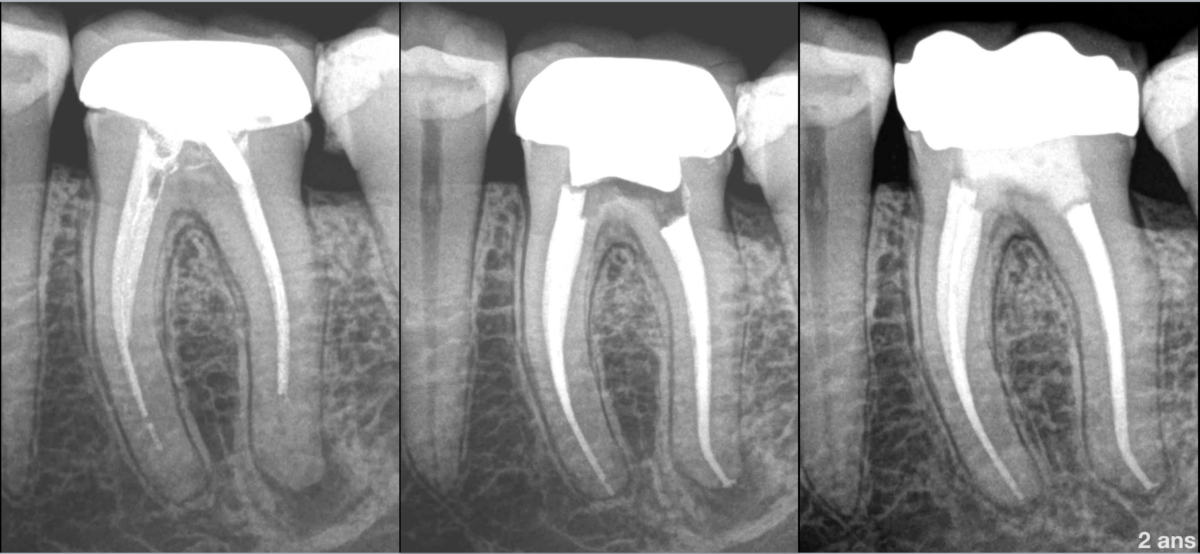

🔍 𝐐𝐮𝐞𝐥 𝐞𝐬𝐭 𝐥’𝐨𝐛𝐣𝐞𝐜𝐭𝐢𝐟 𝐝’𝐮𝐧 𝐫𝐞𝐭𝐫𝐚𝐢𝐭𝐞𝐦𝐞𝐧𝐭 𝐜𝐚𝐧𝐚𝐥𝐚𝐢𝐫𝐞 ?

🦷 𝐑𝐞𝐦𝐞𝐭𝐭𝐫𝐞 𝐥𝐚 𝐝𝐞𝐧𝐭 𝐝𝐚𝐧𝐬 𝐮𝐧 𝐞𝐧𝐯𝐢𝐫𝐨𝐧𝐧𝐞𝐦𝐞𝐧𝐭 𝐛𝐢𝐨𝐥𝐨𝐠𝐢𝐪𝐮𝐞 𝐟𝐚𝐯𝐨𝐫𝐚𝐛𝐥𝐞 à la cicatrisation osseuse ou au maintien de sa santé.